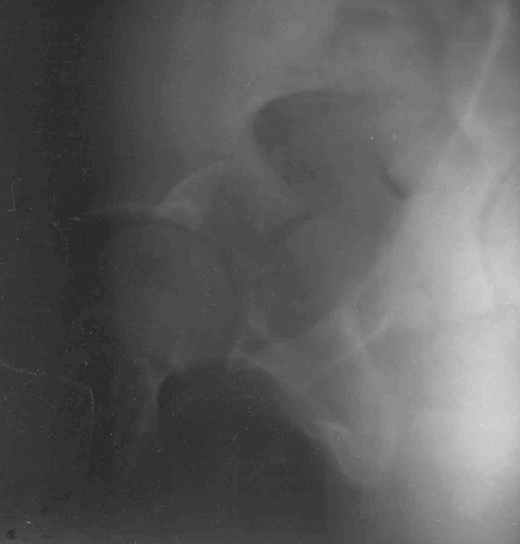

11Judet 1Judet 2

Согласно договорённости с А.В. Рунковым высылаю КТ и скиаграмму (со сканами рентгенограмм опять проблемы) 29-летнего пациента после автотравмы. С Уважением Андрей Стасюк

1) Оперативное лечение: открытая репозиция фрагмента заднего края вертлужной впадины (через задний доступ), фиксация винтами. 2) Скелетное вытяжение сроком до 4 месяцев (для разгрузки сустава). 3) Курс хондропротекторов, витаминов, сосудистых препаратов (в течение срока лечения скелетным вытяжением).

Там смещение есть и на уровне свода тоже...